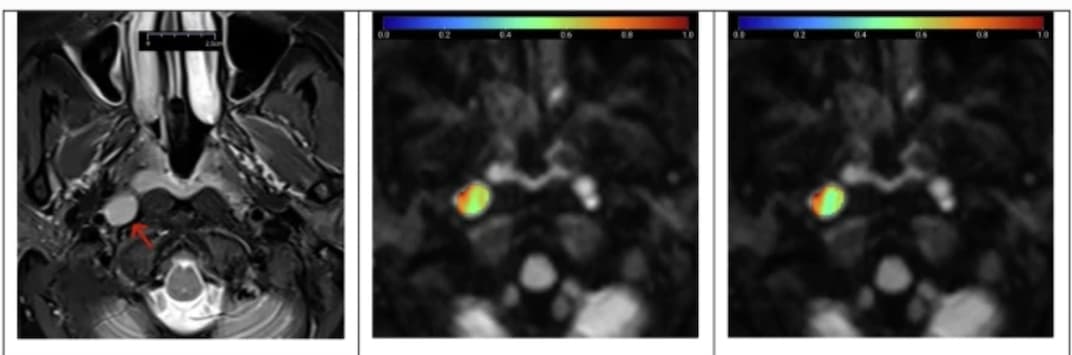

L'imagerie TEP va devenir la principale modalité de diagnostic moléculaire et de traitement personnalisé dans les années à venir. C’est pourquoi Philips a décidé d’investir dans le développement de la nouvelle technologie TEP-scan vereos. Cette modalité est 100% numérique, dotée de la technologie Comptage Photonique Numérique (Digital Photon Counting), brevet Philips, associant une sensibilité inédite, une meilleure résolution d’image et une précision quantitative améliorée par rapport aux systèmes analogiques.

La technologie numérique Philips de comptage photonique convertit directement la lumière en signal numérique. Presque aucun bruit ne s’étant introduit lors de cette conversion, on obtient un meilleur rapport signal-bruit et une plus grande sensibilité. De plus, si l’on associe à cela une résolution temporelle élevée (temps de vol), on améliore le contraste d’image, ce qui facilite la détection des lésions et le diagnostic du médecin avec des doses radioactives injectées très faibles.